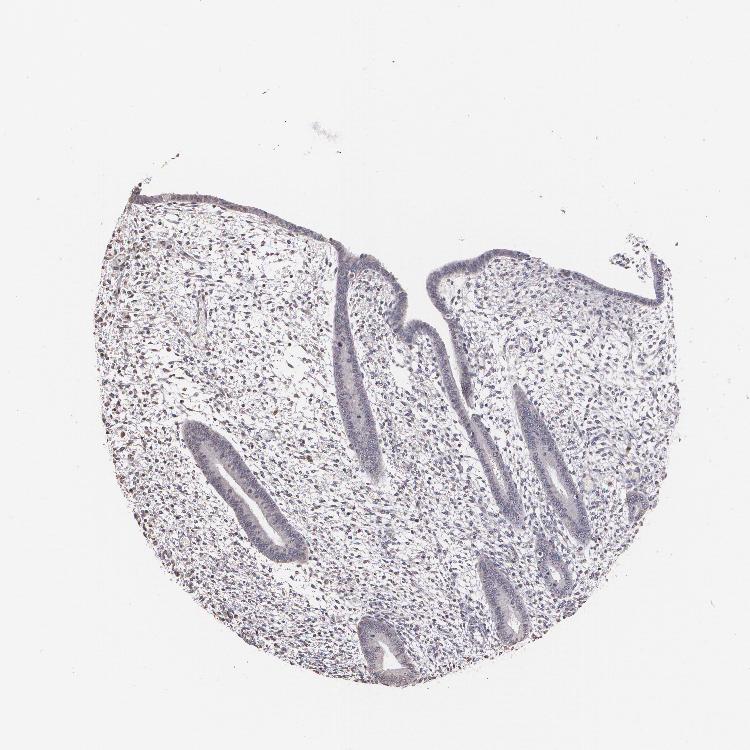

ENDOMETRIUM 2 - Antibody stainingi

Antibody staining in the annotated cell types in the current human tissue is reported as not detected, low, medium, or high, based on conventional immunohistochemistry profiling in selected tissues. This score is based on the combination of the staining intensity and fraction of stained cells.

Each image is clickable and will lead to virtual microscopy that enables deeper exploration of all samples and also displays staining intensity scores, fraction scores and subcellular localization as well as patient and tissue information for each sample.

Antibody CAB002008Antibody CAB002009

Cells in endometrial stroma Not detectedLow

Glandular cells Not detectedLow